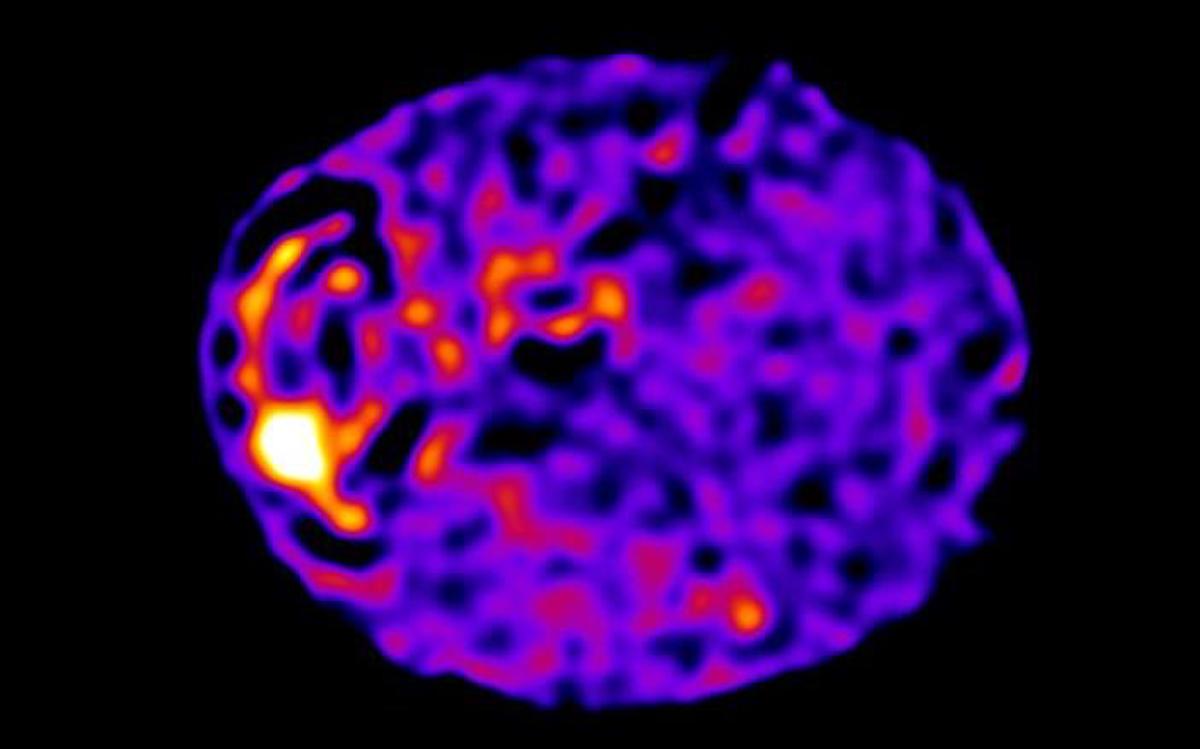

Las primeras imágenes de la web de toda la célula se capturaron con la ayuda de técnicas informáticas similares a las utilizadas para obtener la primera imagen de un agujero negro. Foto: Universidad de Edimburgo.

El equipo de Edimburgo descubrió la red celular que organiza toda esta dinámica, estudiando el movimiento de las moléculas de calcio cargadas eléctricamente dentro de las células.

Para ello utilizaron microscopios de gran potencia y algoritmos informáticos similares a los utilizados para obtener la primera imagen de un agujero negro.

El equipo de Edimburgo descubrió la red celular que organiza toda esta dinámica, estudiando el movimiento de las moléculas de calcio cargadas eléctricamente dentro de las células.

Para ello utilizaron microscopios de gran potencia y algoritmos informáticos similares a los utilizados para obtener la primera imagen de un agujero negro.